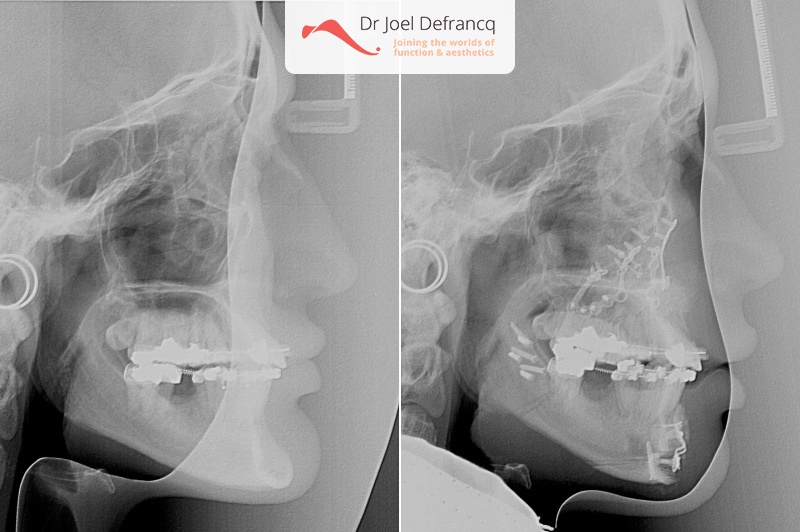

Kaakchirurgie

- Verlenging onderkaak (BSSO)

- Verlenging bovenkaak (Le Fort I)

- Vertikale verlenging bovenkaak (Le Fort I)

- Kinchirurgie